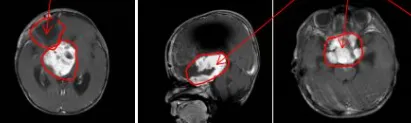

为保障患儿安全及提高切除率,巴教授与Concezio Di Rocco教授决定实施联合手术。通过额骨颅骨开颅术和大脑半球间穹窿入路切除肿瘤至Monro孔(室间孔),并沿脑室壁向中脑行进。右侧视神经被肿瘤浸润包裹,但左侧视神经被小心地从肿瘤肿块中剥离,垂体腺和垂体柄得到妥善保护,无术中并发症。第三脑室占位完全切除,鞍上占位基本全切,视神经及周围血管保持完整。

术后结果

拔管后患儿四肢活动正常。在密切监测血钠及液体平衡情况下,调整去氨加压素用药。返回普通病房后,巴教授与内分泌学家协作,使用去氨加压素治疗尿崩症并优化垂体激素替代方案。患儿顺利出院,临床症状较入院前明显改善。